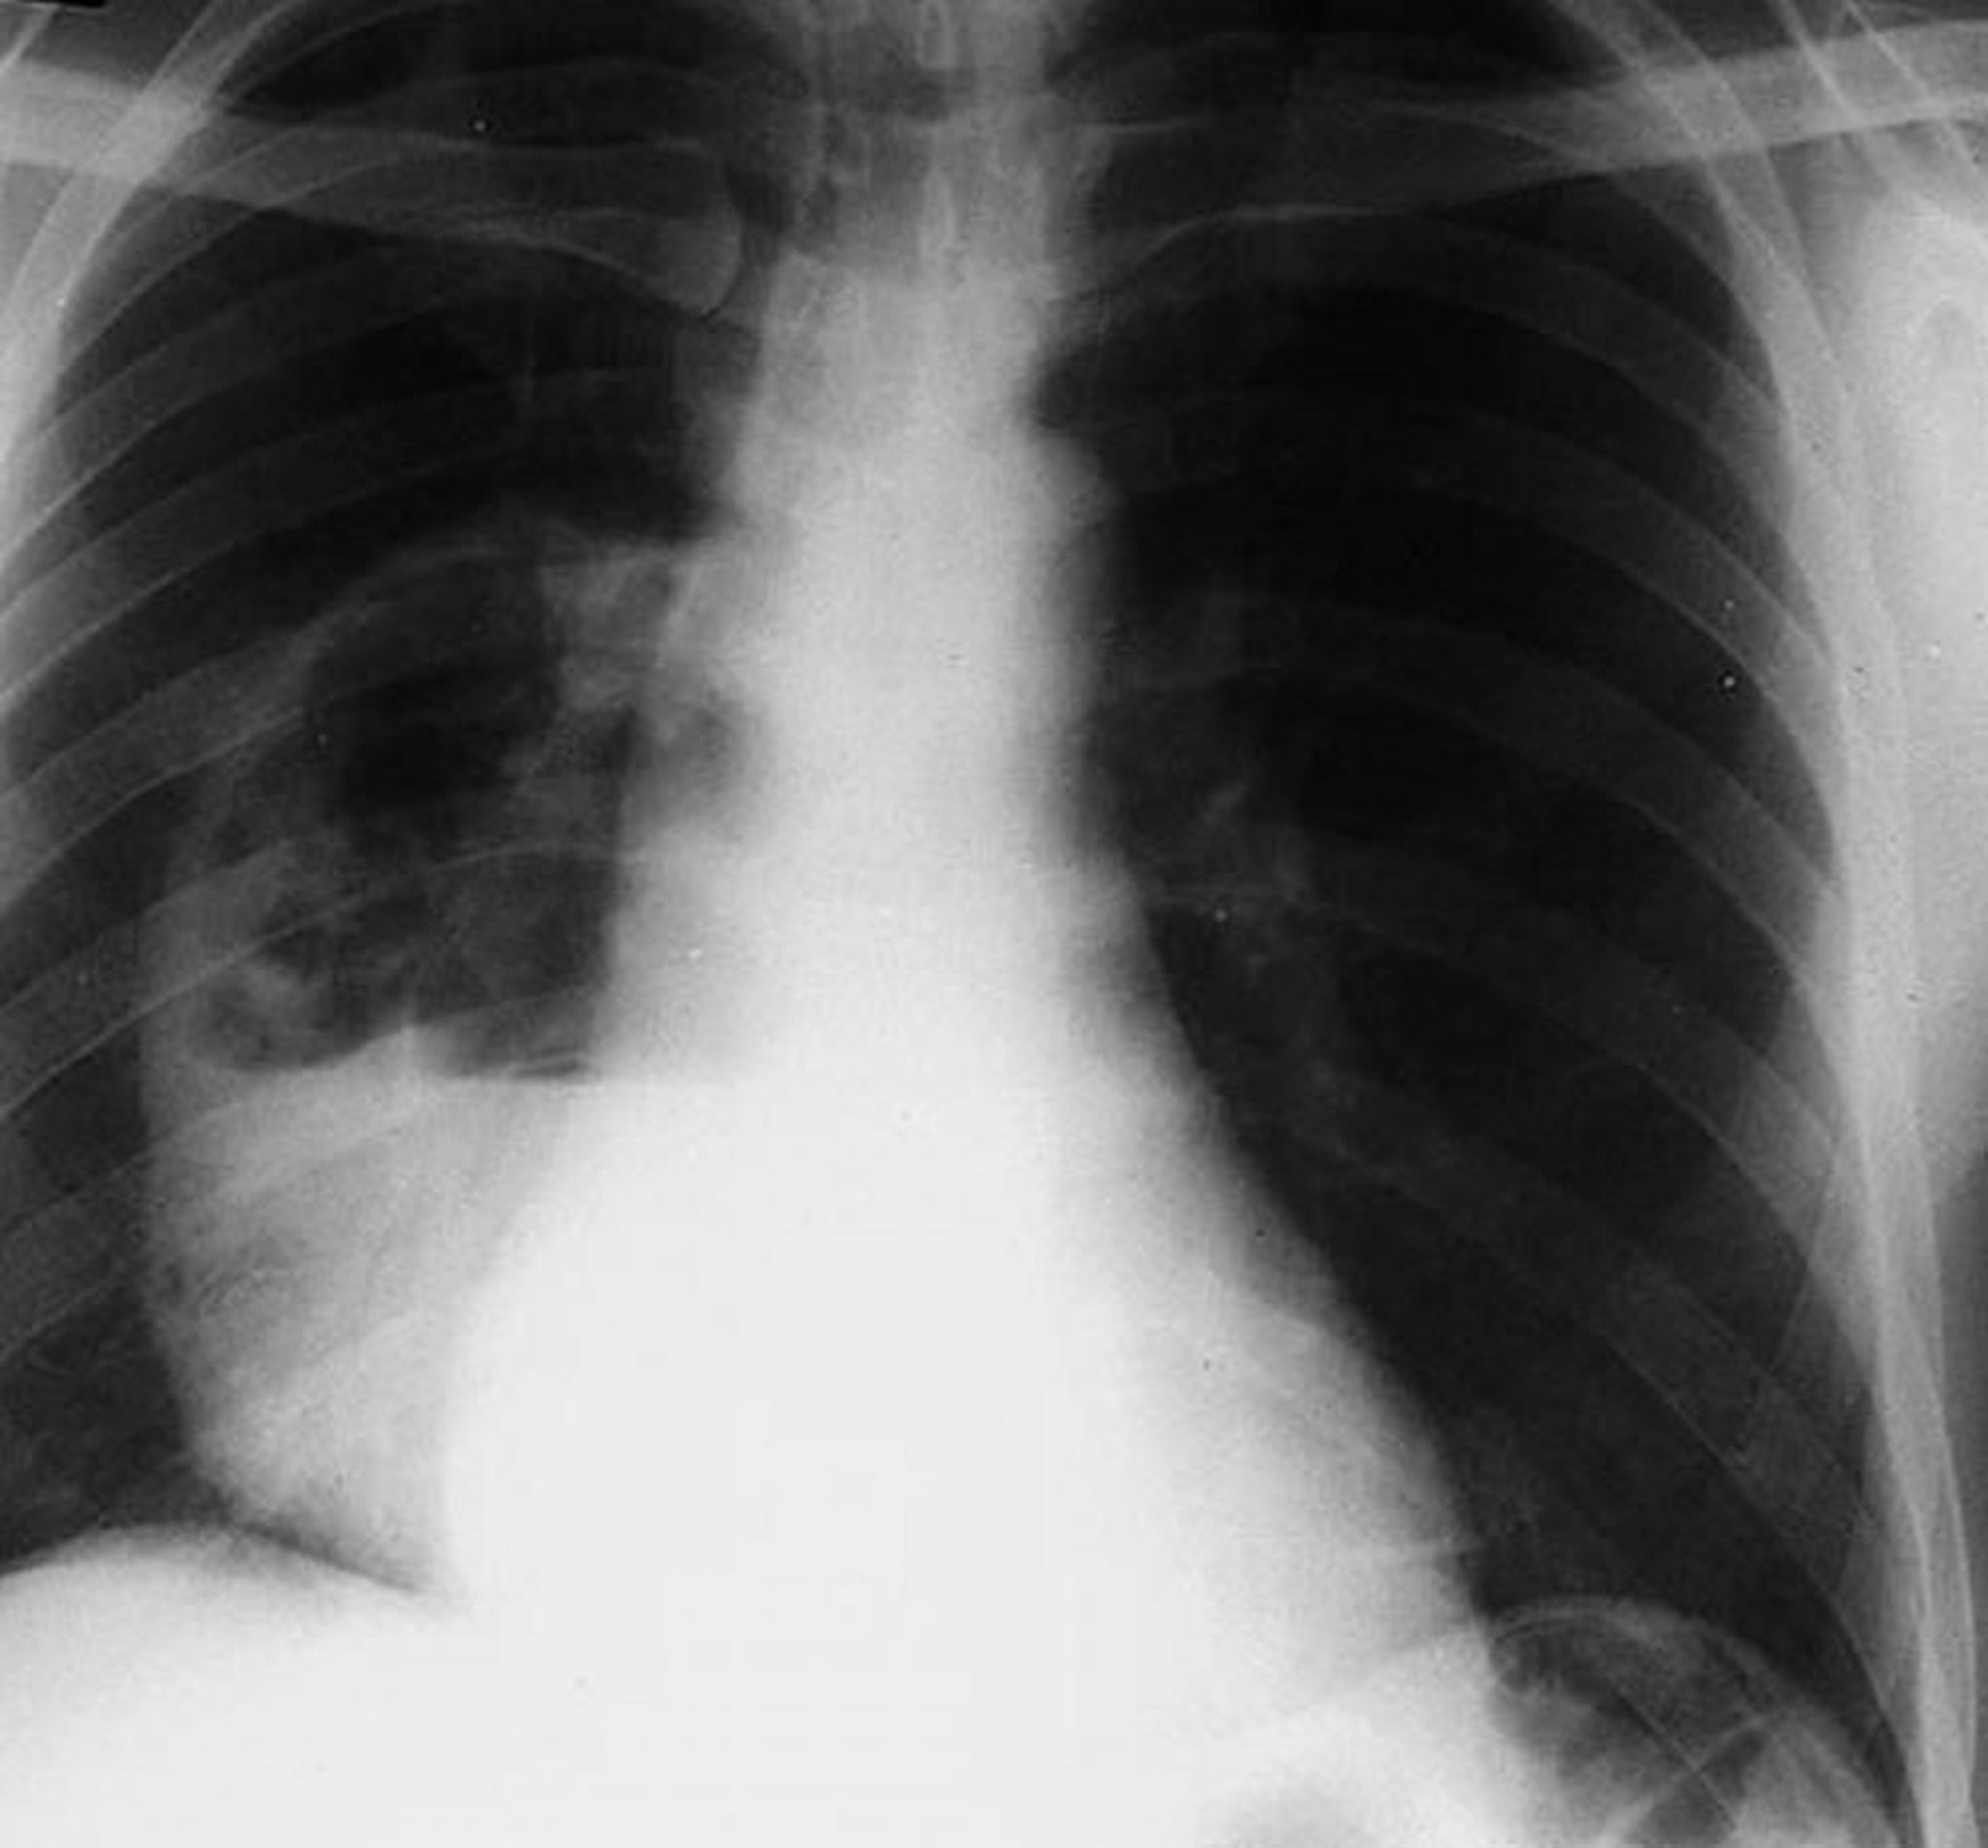

Абсцесс легкого (рентгенограмма)

На этом снимке представлен большой абсцесс правой нижней доли, демонстрирующий полость с уровнем жидкости и газа. Белые стрелки указывают на границу абсцесса, обозначая стенки, отделённые от паренхимы лёгкого. Чёрные стрелки обозначают уровень, на котором встречаются воздух сверху и жидкость снизу.